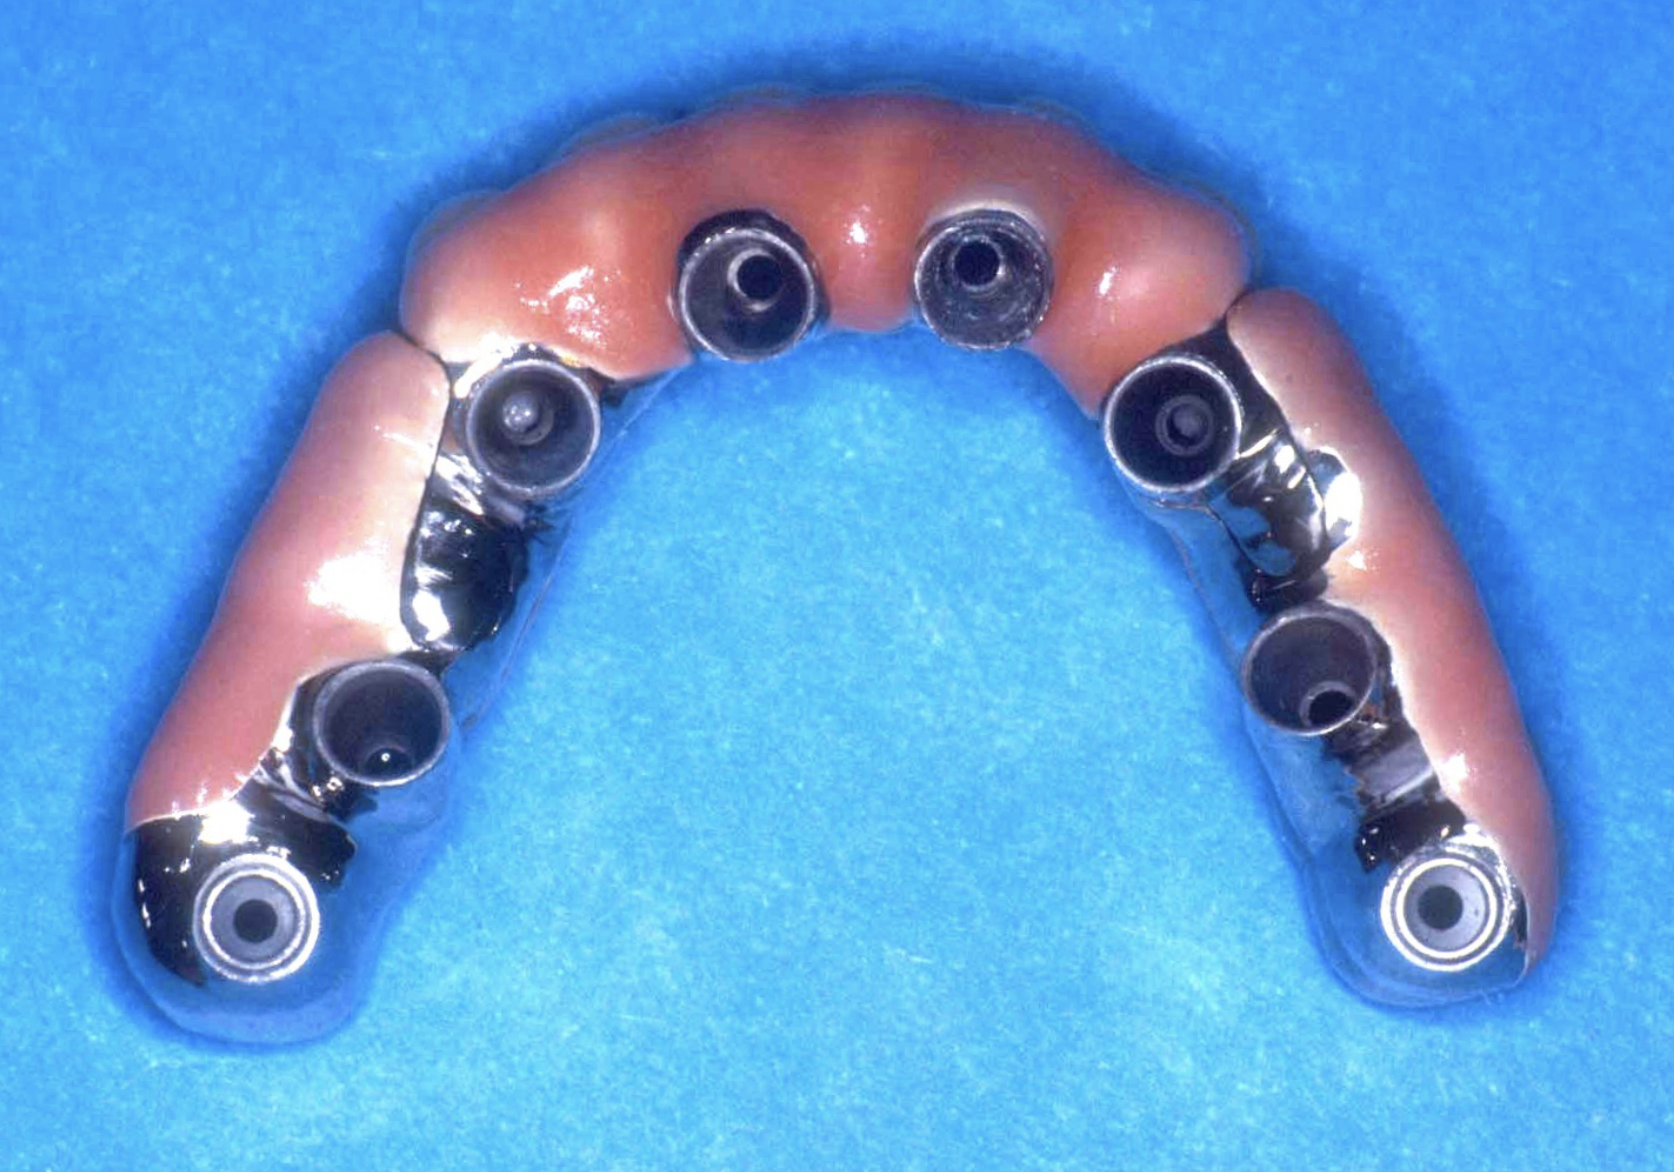

Patient Factors that May Contraindicate Fixed Implant-supported Prosthetics

(42.) Fixed-removable prosthesis.

Figure 42

(43.) Fixed-removable prosthesis.

Figure 43

(44.) Fixed-removable prosthesis.

Figure 44

(45.) Fixed-removable prosthesis.

Figure 45